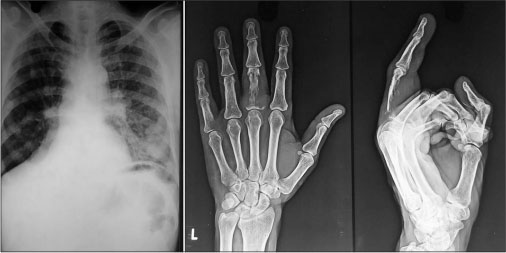

We herein report a case of a 56-year-old male, who presented to us with complaints of swelling over the nose associated with nasal blockade and discharge for past 1 year with increase in growth for past 3 months, swelling and pain in the left middle finger for past 3 months, and difficulty in breathing for past 1 month. The physical examination revealed swollen middle finger of left hand and exophytic mass replacing the nasal cavity [Figure 1]. The X-ray (anteroposterior and lateral views) of the left hand demonstrated lytic destruction of distal phalanx of middle finger [Figure 2]. The chest X-ray (posteroanterior view) demonstrated bilateral lung metastases [Figure 2], which was further confirmed by contrast-enhanced computed tomography (CECT) of thorax [Figure 3]. CECT of head and neck revealed an enhancing lesion in nasal cavity with the destruction of nasal cavity and extension into maxillary sinus and nasopharynx [Figure 3].

|?Figure. 2? X-ray of chest (postero-anterior view) and left hand (anteroposterior and lateral view)